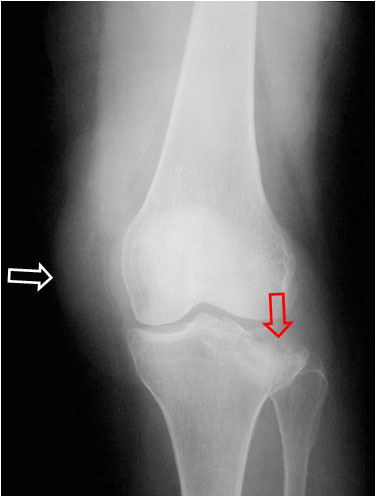

SIGNO DEL SURCO FEMORAL LATERAL

Signo indirecto de rotura del ligamento cruzado anterior (LCA) en la radiografía simple. Se trata de una depresión anormalmente profunda del surco cóndilo-patelar lateral o surco femoral lateral (flecha). Este surco es una pequeña depresión normal en la superficie articular del cóndilo, entre la curvatura que articula con la rótula y la que gira sobre la tibia. El surco anormalmente profundo se produce en la fractura osteocondral impactada, que acontece al tiempo que la rotura del LCA, ya que el mecanismo de ambas lesiones es el mismo: rotación de la articulación y valgo forzado, en el que chocan el platillo tibial contra el cóndilo femoral.

Imágenes de resonancia magnética de la rodilla, que muestran cortes sagitales de una secuencia potenciada en T1. La fotografía de la izquierda muestra como el surco femoral lateral es anormalmente profundo y se acompaña de una disminución de la señal del hueso adyacente por edema medular (flecha blanca). A la derecha, corte en el que debería verse el LCA, ausente por rotura.